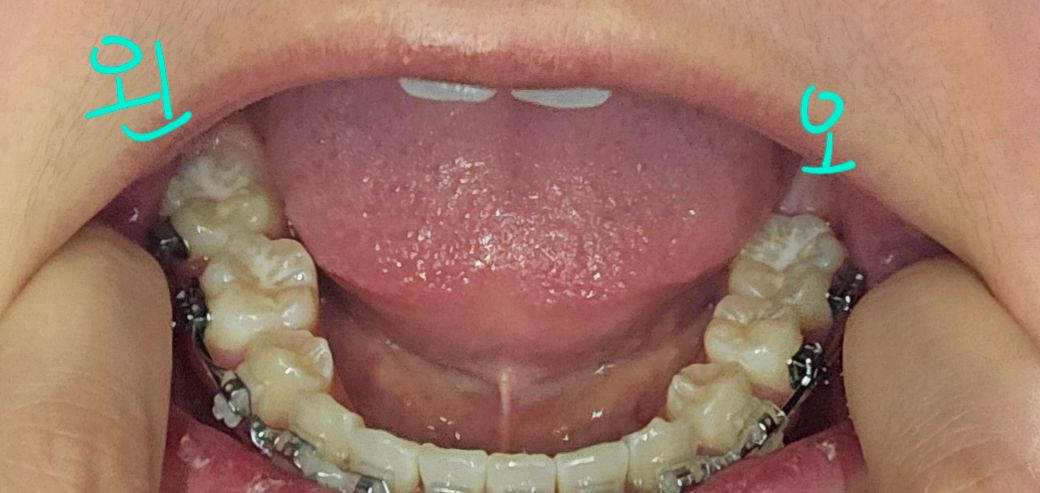

왼쪽 위아래는 둘다 작은 어금니, 오른쪽 위는 작은 어금니를 발치했는데 아래는 큰 어금니가 많이 썩어있어서 발치를 하고 교정 진행했어요

빈공간은 없고 밥 먹을때도 괜찮아요 확실하진 않지만 위 치아랑 닿기는 닿는 것 같아요.. 근데 사진처럼 저렇게 보이는데 괜찮을까요?

큰 어금니는 모두 있고 작은 어금니를 발치하신 것으로 보이며 교정 시 작은어금니를 발치하는 경우는 많습니다.

사진상으로 크게 문제가 잇어 보이는건 없는거 같습니다. 가장 후방치아에 대합되는 치아가 잇다면 추후에 임플란트 식립을 하셔야될수도 잇을것같습니다.

위 사진상으로는 교합을 평가하기 어렵고요. 사진상 오른쪽 (실제로는 왼쪽) 두번째 큰어금니 빈 공간은 임플란트를 심어줄 순 있습니다.